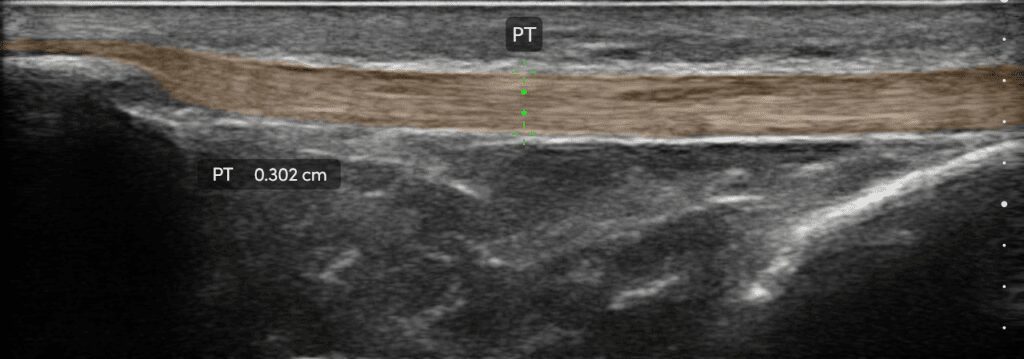

The Clarius L15 HD3 is the perfect probe for sports medicine.